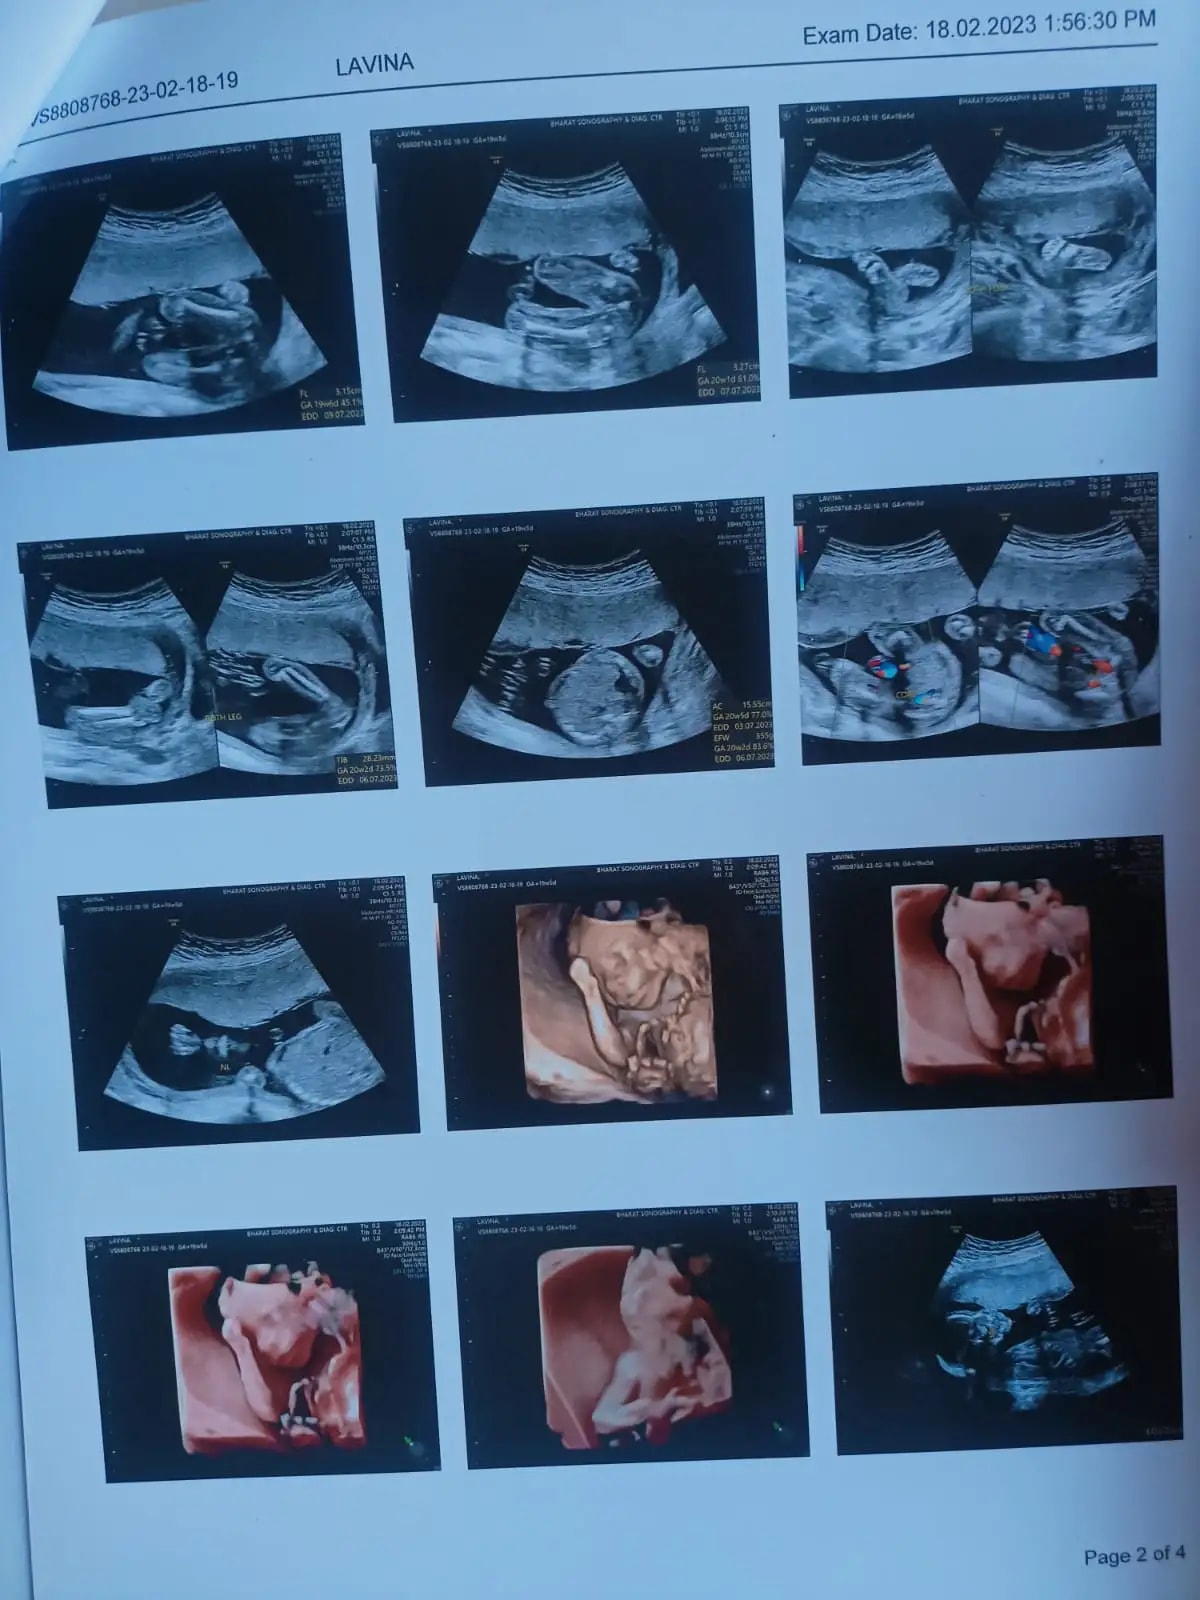

Q: Any guesses ??

A: Baby girl... See more

A: girl hsaaf show hora h uski legs k bich khuch bhi ni h it means girl h ... See more